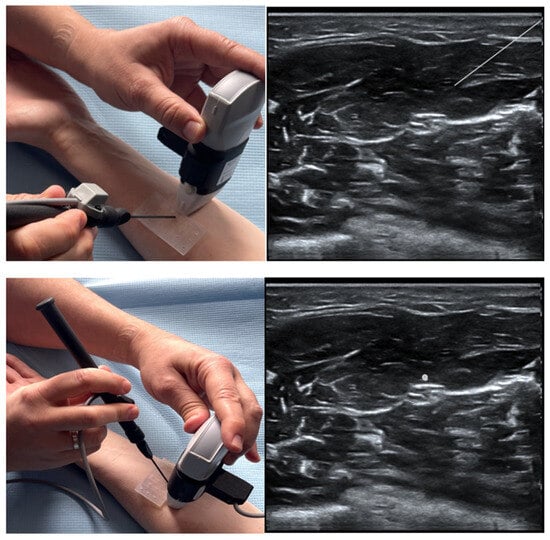

- Shevlin, S.P.; Turbitt, L.; Burckett-St Laurent, D.; Macfarlane, A.J.; West, S.; Bowness, J.S. Augmented Reality in Ultrasound-Guided Regional Anaesthesia: An Exploratory Study on Models With Potential Implications for Training. Cureus 2023, 15, e42346. [Google Scholar] [CrossRef]